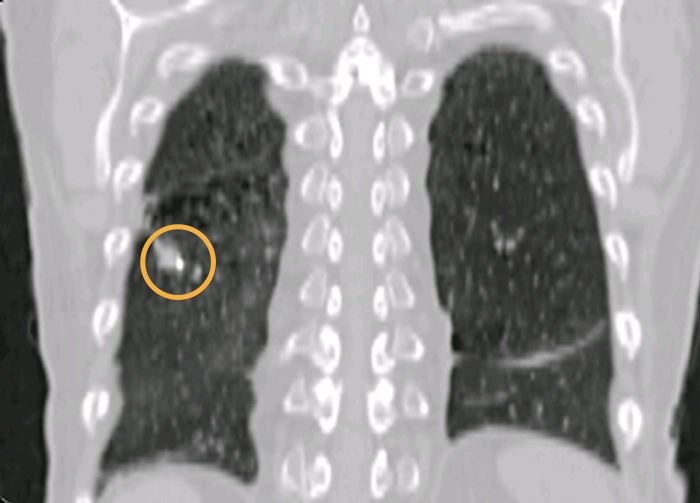

Biopsy marking Radiation therapyLung

Lung tumors can often be visualized with cone-beam CT but there are cases that can benefit from using fiducial markers, e.g. when there is atelectasis or when the tumor edges as blurry. Gold Anchor’s industry leading thin needles drastically reduces the risk of transthoracic implantation. With the Gold Anchor Introducer the markers can also be placed using bronchoscopy.